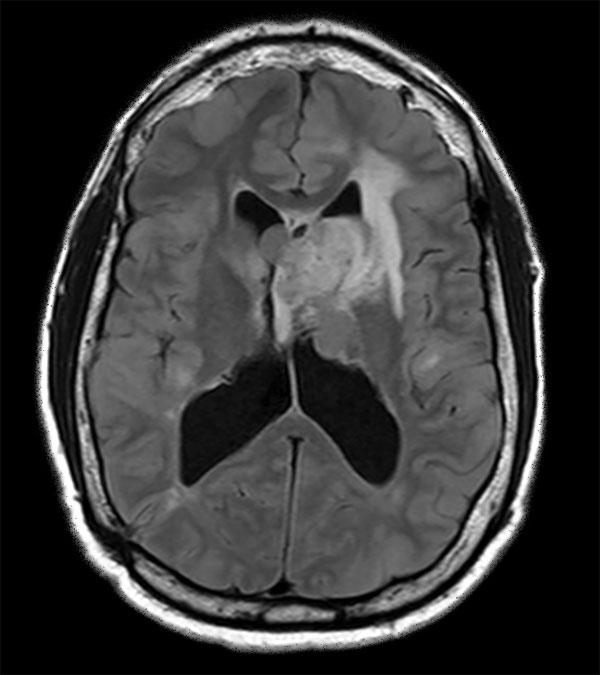

Axial T2w FLAIR